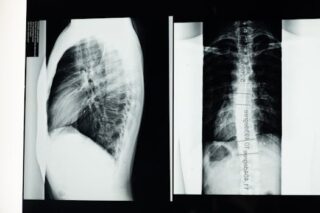

When people hear the term “bamboo spine,” they might not immediately understand its implications for health. This condition, characterized by the appearance of a spine that resembles a bamboo stick on X-ray, is associated with a type of arthritis called ankylosing spondylitis. It involves inflammation that can lead to the fusion of vertebrae, severely affecting mobility and posture.

Bamboo spine is most commonly linked to ankylosing spondylitis, a chronic inflammatory condition. The inflammation primarily affects the spine and the sacroiliac joints, where the spine meets the pelvis. Over time, this inflammation may lead to pain, stiffness, and in severe cases, the vertebrae can fuse together, creating that characteristic bamboo-like appearance seen in X-rays.